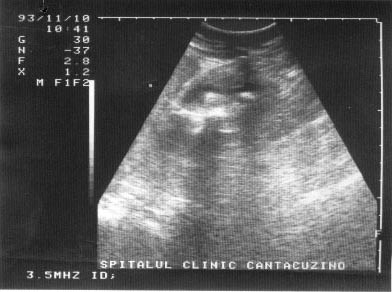

Imaginea transsonica

Structurile lichidiene (sangele, bila, secretiile digestive, continutul chistelor, ascita, colectia pleurala) sunt strabatute de catre ultrasunete in totalitate, fara a exista nici un fel de reflexii pe traseul acestora. Imaginea ecografica, fiind expresia unei "lipse de ecouri", va avea aspectul opus structurilor ecogene, respectiv culoarea neagra. O structura lichidiana este definita in ecografie prin termenul de transsonic.

Exemple:

structuri transsonice normale: colecist, vezica urinara, lumen vascular;

structuri transsonice patologice: chistul, continutul necrozat al unui abces sau al unei tumori maligne.

Figura 1. Vezica urinara

Figura 2. Chist renal stang situat in treimea medie

Figura 3. Chist ovar drept

Figura 4. Chist hepatic